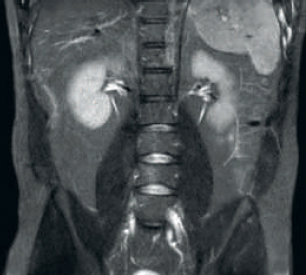

dStream Empfang

Das Ergebnis: Ein verbessertes SNR und höhere Bildauflösung